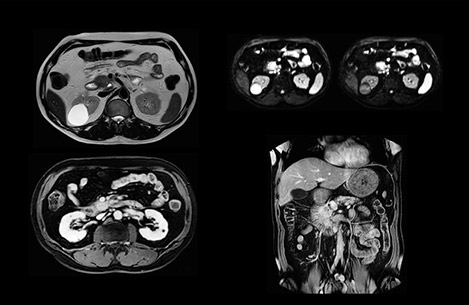

“Our liver exams are quite fast,” says Dr. Baumann. “If the patient tolerates it, we use an arms-up position to reduce the FOV and speed up the exam with dS SENSE.” “We acquire one transversal high resolution T2-weighted sequence with 3 mm slice thickness, for example for pancreas or liver lesions. Then we also add a T2 fat suppressed MultiVane XD SPIR sequence. We perform these two routinely in our liver imaging. We use high dS SENSE factors to significantly shorten scan times to 2-4 minutes, which can improve our protocol; it’s a very robust scan.” “We include mDIXON for the dynamic sequences because of the robust and homogeneous fat suppression we get with that. We had been using eTHRIVE, but we are now quite happy with mDIXON. Sometimes we use a medication to calm the bowels, to further improve the image quality.”